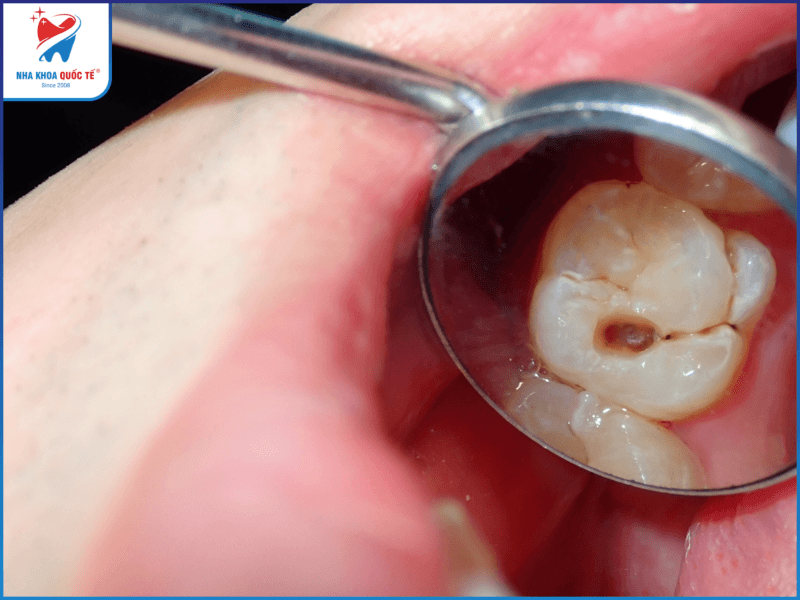

• Nhiễm trùng răng miệng kéo dài

Đổi màu răng là dấu hiệu phát hiện bệnh u ở răng sớm nhưng thường dễ bị bỏ qua. Chỉ đến răng miệng gặp một số tình trạng nghiêm trọng hơn như chảy mủ, đau ở vùng có u, lung lay răng, sưng mặt… thì mới được người bệnh chú ý và đi tới nha khoa, bệnh viện khám.